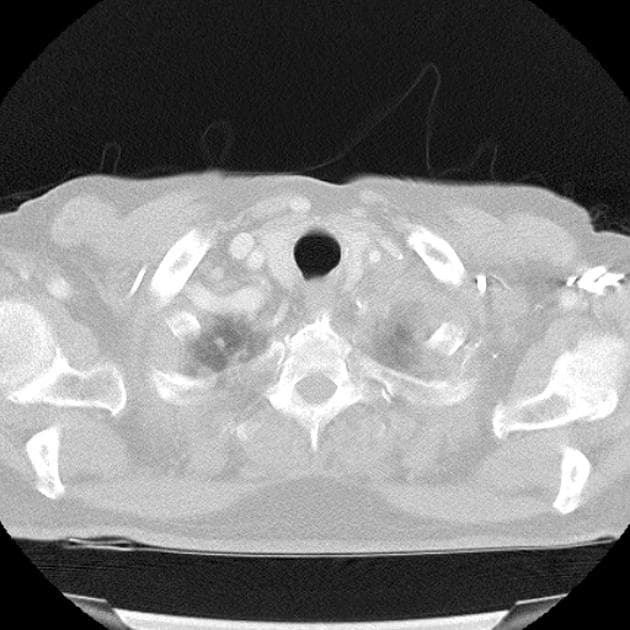

- Khối rất giới hạn rõ (well-circumscribed) ở cổ tử cung đoạn thấp, với lớp niêm mạc tử cung còn nguyên vẹn.

- Siêu âm ban đầu phát hiện khối lớn ở đoạn thấp tử cung.

- Sinh thiết ghi nhận u lympho cổ tử cung (lymphoma of cervix).

- CT cắt lớp vi tính giai đoạn (staging CT) vùng cổ, lồng ngực và bụng không phát hiện bất thường nào.

- U lympho cổ tử cung (lymphoma of cervix) đơn độc khá hiếm gặp và có thể biểu hiện hình ảnh với những dấu hiệu hiếm như trường hợp này.

U lympho cổ tử cung (lymphoma of cervix)

U lympho cổ tử cung là một biểu hiện ngoại hạch hiếm gặp của u lympho không Hodgkin, trong đó tổn thương khu trú riêng lẻ tại cổ tử cung là rất bất thường. Bệnh thường khởi phát với các triệu chứng không đặc hiệu như rối loạn cảm giác vùng chậu hoặc chảy máu bất thường. Chẩn đoán hình ảnh thường phát hiện khối u giới hạn rõ, có thể bắt chước các khối u lành tính như u cơ trơn hoặc các khối u ác tính biểu mô. Việc bảo tồn lớp niêm mạc tử cung, như trong trường hợp này, có thể là dấu hiệu gợi ý về nguồn gốc không phải biểu mô. Chẩn đoán chủ yếu dựa vào phân tích mô bệnh học và miễn dịch hóa học vì hình ảnh học không đặc hiệu. CT giai đoạn không thấy tổn thương hệ thống hỗ trợ chẩn đoán u lympho cổ tử cung nguyên phát đơn độc. Nhận biết rõ về bệnh lý này là rất quan trọng để tránh chẩn đoán nhầm và đảm bảo điều trị ung thư phù hợp.